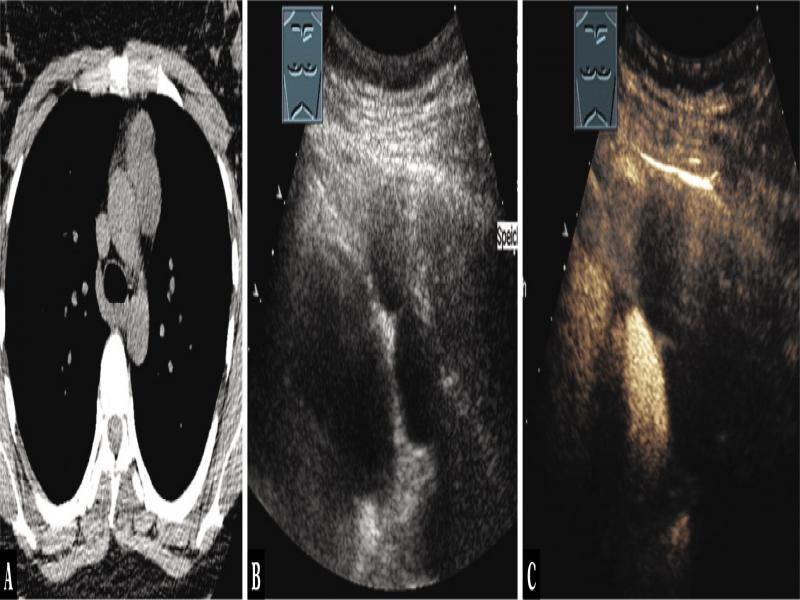

Fig. 15.

A 71-year-old female patient with thoracic pressure sensation and a mediastinal tumor in the anterior mediastinum on computed tomography as well as an additional pleural lesion (A). Thoracic ultrasound indicated a hypoechoic lesion (B); the tumor showed marked homogeneous enhancement on contrast-enhanced ultrasound (C). Ultrasound-guided biopsy was performed, and the diagnosis of thymic carcinoma B1 was histologically confirmed